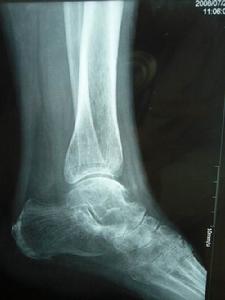

細胞、骨質細胞、髓質細胞(血管和神經)發生了壞死,致骨組織營養中斷或嚴重不足,使骨的代謝障礙,局部骨組織失去了營養,即為骨壞死。骨壞死原則上分為兩大類:一類是由於細菌感染所致的骨壞死,如:骨髓炎、骨結核、化膿性關節炎等。另一類是因缺血造成的骨壞死,如外傷、飲酒、激素藥、寒濕、肝腎虧虛、骨質疏鬆、扁平髖、脊髓異常空洞症等導致的骨壞死。人體任何部位都可能發生骨壞死,臨床以手舟骨、足舟骨、距骨、肱骨頭、肋骨、髕骨、鎖骨、股骨頭為多見,尤以股骨頭髮生率最高。骨壞死發生在股骨頭部位,就叫股骨頭壞死。

①外傷 股骨頸骨折、扭傷、摔傷、髖關節脫位、髖臼發育不全易發生股骨頭壞死,其發生的時間,一般認為絕大多數在骨折後1~5年,最早可以在傷後2~3個月出現,發生率一般在75%~95%,骨折手術後大部分均可發生骨壞死。髖部損傷(包括髖關節脫位、股骨頸骨折、轉子骨折等)直接影響局部的血運供給,尤其是股骨頭的供血不足,而致股骨頭壞死。髖關節脫位合併骨折,壞死率高達90%。如超過24小時未整復的骨折脫位,股骨頭會100%發生壞死。

是診斷該病最簡單、最實用的方法,但敏感性差,早期單憑X線片不易診斷。骨壞死早期表現為骨質正常或輕度疏鬆,也可出現病變區骨密度相對均勻增高現象,隨後可見負重區有楔狀硬化帶或骨組織囊性病灶形成,進一步出現與關節面平行的“新月狀透亮帶”,關節間隙增寬。最後出現軟骨下骨板及關節面塌陷,骨輪廓改變,階梯狀不連續,骨壓縮加重,同時髖臼關節面也受損,關節間隙狹窄、骨贅形成,整個關節呈現退行性關節炎改變。